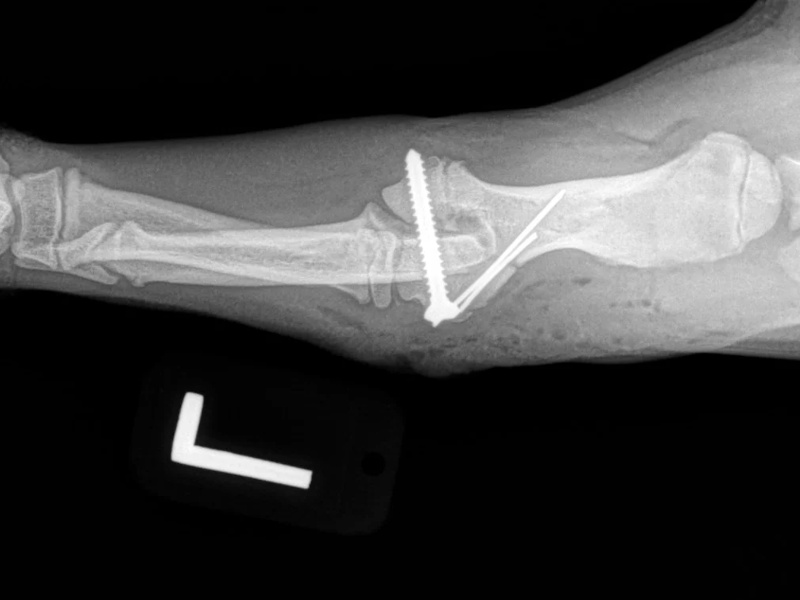

Post Surgical Radiographs

While the patient is still anesthetized, the patient is taken into radiology for post-surgery radiographs (X-rays). The radiographs are assessed to ensure the apparatus FASTak screw and toggle are appropriately positioned.

An osteotomy is a surgical cut in a bone. In the cruciate deficient stifle, a cut is made in the top of the tibia. The top portion of bone that contains the articular surface is rotated to level it. The two pieces of bone are held in place with a metal plate and screws.

While the patient is still anesthetized, the patient is taken into radiology for post-surgery radiographs (X-rays). The radiographs are assessed to measure the new tibial plateau angle. We are aiming for 5-6 degrees relative to the long axis of the tibia. The apparatus (plate and screws) are assessed for size and appropriate position.